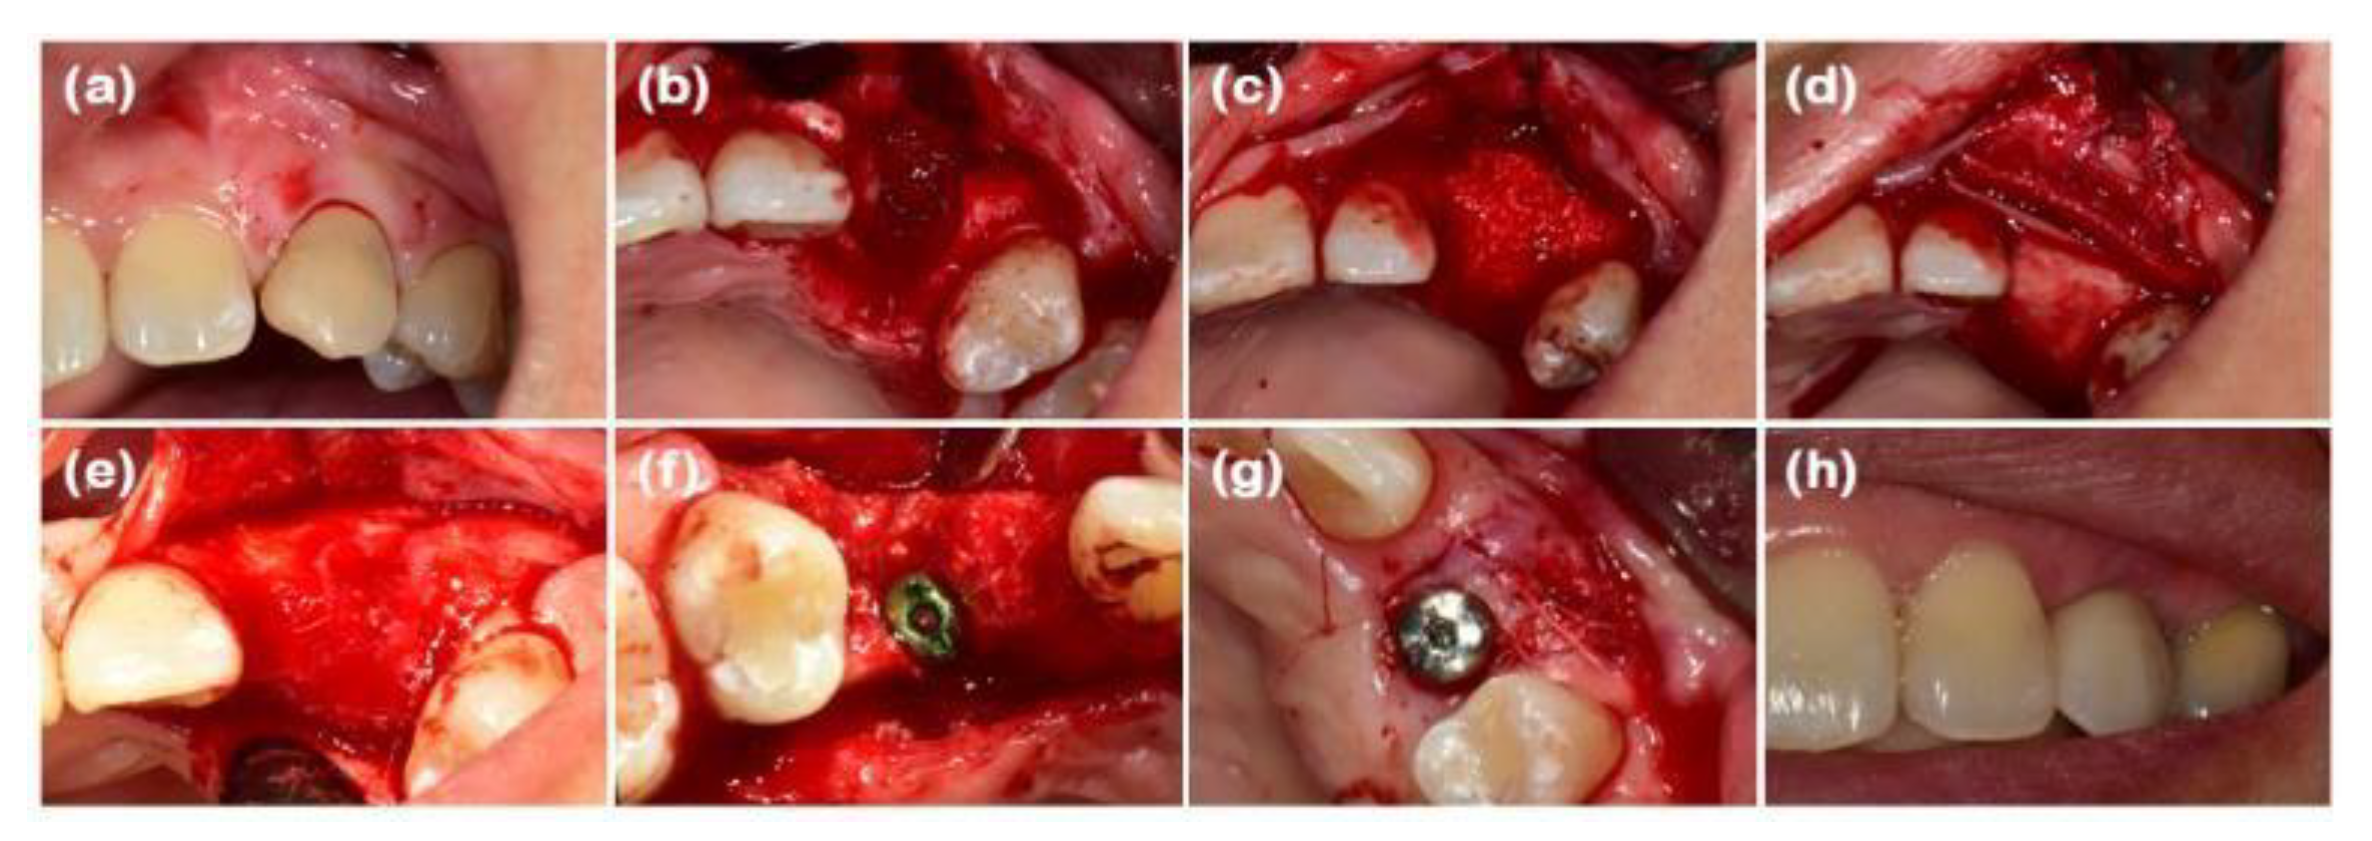

Figure 1. Clinical photographs of case 1. (a) Initial presentation of the maxillary left canine prior to extraction. (b) Buccal bone defect exposed after full-thickness flap elevation. (c) Defect filled with deproteinized bovine bone mineral (DBBM). (d) Bone graft area covered with soft-type resorbable collagen membrane, hard-type resorbable collagen membrane on the buccal side, and finally, collagen matrix in the outer position. (e) Full-thickness flap elevation reveals adequate bone volume. (f) Implants placed in the sufficiently augmented bone area. (g) Second implant surgery performed. (h) Definitive prosthesis connection.

After performing full-mouth scaling, #23 was extracted and ARP was performed a month later. A horizontal incision was made on the palatal side, and a full-thickness flap, including the interdental papilla, was elevated buccally. The periapical cystic lesion was removed, revealing extensive horizontal and vertical bone defects as well as buccal bone plate loss (Figure 1b). A synthetic bone graft material mixed with collagen (Osteon 3 collagen® (biphasic calcium phosphate with collagen), Genoss Co. Ltd., Suwon, Korea) was inserted into the extraction socket, and to fully cover the alveolar crest, a resorbable collagen membrane with soft-type stiffness (Collagen membrane 2®, Genoss Co. Ltd.) was applied. To reconstruct the buccal bone wall, a resorbable collagen membrane with medium-type stiffness (Collagen membrane P®, Genoss Co. Ltd.) was placed over the buccal side of the socket. Due to the extensive buccal bone loss, a soft tissue graft between the membrane and the flap was necessary to compensate for soft tissue collapse and delayed healing. A xenogenic collagen matrix (Collagen graft 2®, Genoss Co., Ltd.) was inserted buccally and slightly on the crestal area (Figure 1c,d). The area was sutured without tension using 6-0 Vicryl (Ethicon, INC., a Johnson & Johnson company, Somerville, USA) and 5-0 Black nylon (AILEE Co., Ltd., Busan, Korea), and intentional secondary healing (open healing) was induced. Upon suture removal 10 days later, secondary healing was observed, with no significant findings other than partial exposure of the bone graft material on the buccal side. The secondary healing area was continuously monitored. After confirming the epithelialization of the soft tissue and the complete regeneration of the interdental papilla between the adjacent teeth, the first implant surgery was performed 9 months after the alveolar ridge augmentation. Prior to implant placement, the width and height of the remaining alveolar ridge were observed to be in good condition (Figure 1e and Figure 2b). A full-thickness flap was elevated, revealing a sufficiently augmented alveolar bone with a width of approximately 6 mm bucco-palatally. The implant was placed in an ideal position (Superline Φ3.5×10 mm, Dentium, Seoul, Korea), and to compensate for the loss of bone graft material due to drilling, additional guided bone regeneration (GBR; Osteon 3 collagen® and Collagen membrane P®, Genoss Co., Ltd.) was performed on the palatal side (Figures 1f and 2c). Five months after the first implant surgery, the second implant surgery was carried out (Figure 1g and 2d). Seven months after the first implant surgery, a customized abutment and veneered zirconia were placed. The interdental papilla between #22 and #23 was regenerated, and 4 mm of buccal keratinized mucosa was stably observed (Figure 1h).

In this study, ARP was performed with flapped surgery in patients who required horizontal and vertical bone augmentation due to the absence of residual bone. A collagen matrix was used to compensate for ridge contraction and to increase the keratinized mucosa around the implants. In case 1, the buccal bone plate at site #23 had been resorbed, resulting in a narrow alveolar ridge width in the bucco-palatal direction, which was insufficient for implant placement. To augment the buccal bone, xenogenic bone graft material, two-types of resorbable collagen membranes, and a xenogenic collagen matrix were applied, sequentially. At the time of implant placement, a ridge width of approximately 5.93mm was observed bucco-palatally, and continuous, intact soft tissue regeneration, including preservation of the interdental papilla, was achieved. In case 2, the bone wall at extraction site #16 had resorbed, necessitating both bone and soft tissue augmentation for predictable implant placement. Periodontal flap surgery was also performed on the adjacent teeth, resulting in a wider incision. A xenogenic collagen matrix was applied to promote adequate soft tissue regeneration. At the time of implant placement, ridge widths of approximately 8.66 and 8.90mm were observed bucco-palatally at sites #16 and #17, respectively, along with a continuous soft tissue contour. In case 3, following the extraction of teeth #31, #32, #41, and #42, the buccal bone plate had been resorbed. After broad ridge augmentation, a xenogenic collagen matrix was applied to aid in soft tissue regeneration and preservation of the interdental papilla. At the time of implant placement, ridge widths of approximately 4.92 and 4.33mm were observed bucco-palatally at sites #32 and #42, respectively, along with continuous soft tissue contour. Upon completion of the implant prosthetics, a natural appearance of the interdental papilla was observed continuously. In case 4, horizontal and vertical alveolar bone defects were observed in explanted sites #46i and #47i, along with a shallow buccal vestibule and insufficient keratinized mucosa. A xenogenic collagen matrix was applied to the buccal and crestal side to ensure sufficient alveolar bone augmentation and keratinized mucosa for implant placement, and the modified Edlan–Mejchar technique was used to deepen the buccal vestibule. At the time of implant placement, ridge widths of approximately 7.90 and 5.58mm were observed bucco-palatally at sites #45 and #47, respectively, while maintaining the natural soft tissue appearance and deepened vestibule. In respect of the anterior teeth in case 1 and case 3, the PES/WES values ​​were measured as 7~8 points, confirming that although the periodontal defects were severe, good esthetic results could be obtained. In the CBCT cross-sectional view and clinical examination of all cases, the alveolar bone width was appropriate for implant placement of narrow diameter or more in the anterior region and regular diameter or more in the posterior region. In addition, the width of the buccal keratinized mucosa was confirmed to be consistently well-maintained at 2 mm or more in all cases. Although there are many opposing views, it is important to secure the presence of keratinized mucosa with more than a 2mm width around the implant for the health and maintenance of the implant [19].